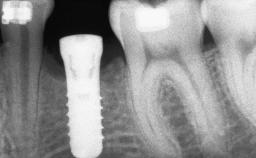

A 47-year-old Caucasian woman with a single-tooth edentulous space at the site of the left maxillary canine was referred for treatment. She had undergone traumatic extraction of this impacted canine several months before referral. Her chief complaint was the dissatisfying appearance of her smile. The patient desired a stable and esthetic rehabilitation of the site. Her dental history showed no evidence of periodontal disease or bruxism. She had no systemic diseases, was not taking any medications, and did not smoke. The extraoral examination revealed a high lip line and an inadequate soft-tissue volume at the defective canine site. Large black triangles were visible between the canine and its adjacent teeth.

# of Implants 1

Type of Implants Two-Piece

Bone Augmentation Staged|Vertical

Bone Volume Deficient vertically or deficient vertically AND horizontally